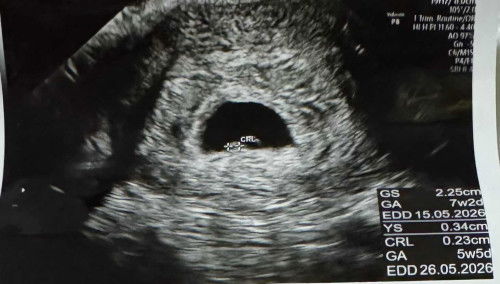

ตั้งครรภ์ 7 วีค 2 วัน แต่ยังไม่เจอตัวเด็กและเสียงหัวใจ ถือว่าปกติมั๊ยคะ

ท้องนี้เป็นท้องที่ 2 แล้วค่ะ ประจำเดือนล่าสุดวันแรกคือ 8/8/25 ซึ่งอายุครรภ์ตอนนี้ประมาณ 7 วีค 2 วัน แต่วันนี้คุณหมอนัดอัลตร้าซาวด์ ปรากฎว่ายังไม่พบน้อง ยังไม่พบเสียงหัวใจ เห็นถุงตั้งครรภ์โตขึ้น ถุงไข่แดงยังโตสวยอยู่ มีแอบเห็นเงาๆ เล็กมากๆ ซึ่งคุณหมอคาดว่าน่าจะเป็นน้อง แต่ยังเล็กมากจึงยังเห็นไม่ชัดเจน คุณหมอนัดอีกทีอีก 2 สัปดาห์ จำได้ว่าสมัยลูกคนแรก 7 วีคก็เห็นน้องแล้ว ตอนนี้แอบกังวลมากเลยค่ะ กลัวไม่เจอน้อง กลัวเป็นท้องลม เนื่องจากตั้งครรภ์รอบนี้ก็อายุเยอะแล้วด้วยค่ะ กังวลไปหมดเลยค่ะ 🥺